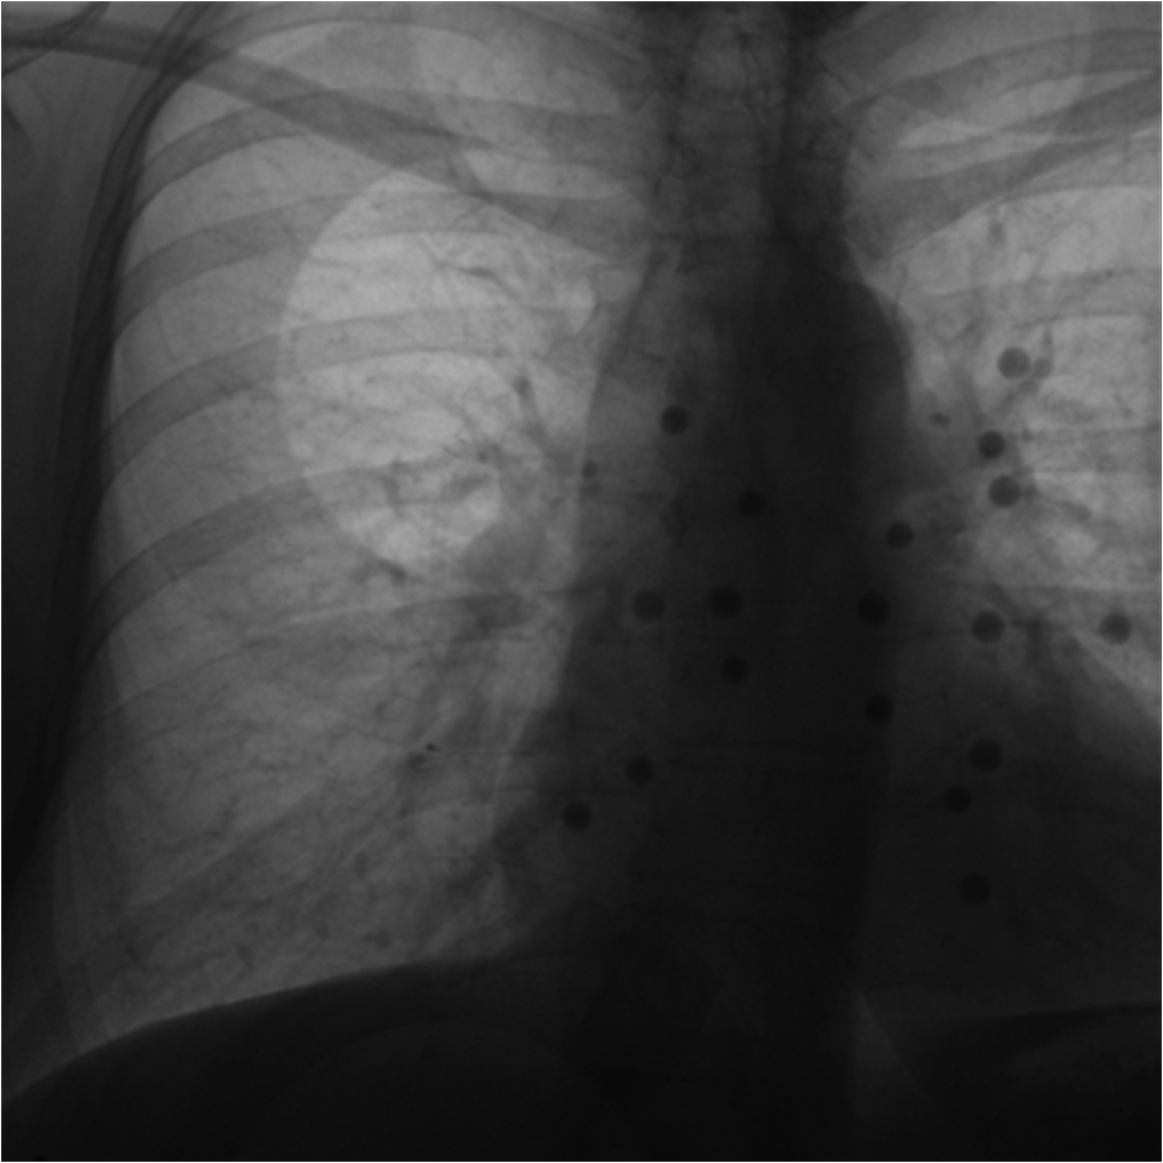

3.4 Phantom experiments

A phantom targeting experiment was conducted to evaluate the accuracy of needle insertion. Fig. 9A shows the experimental setup, including an endoleak phantom, an FG mounting frame, and a Canon Alphenix C-arm (Canon Inc., Tokyo, Japan). Three magnetically tracked needles were inserted into the endoleak phantom. During 2D navigation, the tracked needles (red lines) were projected on the fluoroscopic image, while the actual needles appeared as dark lines. The discrepancies between the two were used to quantify 2D targeting accuracy.

Fig. 9B illustrates the 3D navigation, including 3D reformations, the rendered contrast-enhanced CT volume, and tracked needles. To validate 3D needle insertion accuracy, we acquired a post-insertion non-contrast CT image (Fig. 9C). The inserted needles were clearly visible in three orthogonal views, with the 3D view displaying the inserted needles in silver and the tracked needles in cyan. Needle tip and angle errors were calculated by comparing the tracked needles with their segmented counterparts from the CT image. This process was repeated three times, with a total of nine inserted needles. The overall needle insertion errors were for the tip, and for orientation, as shown in Table 5.